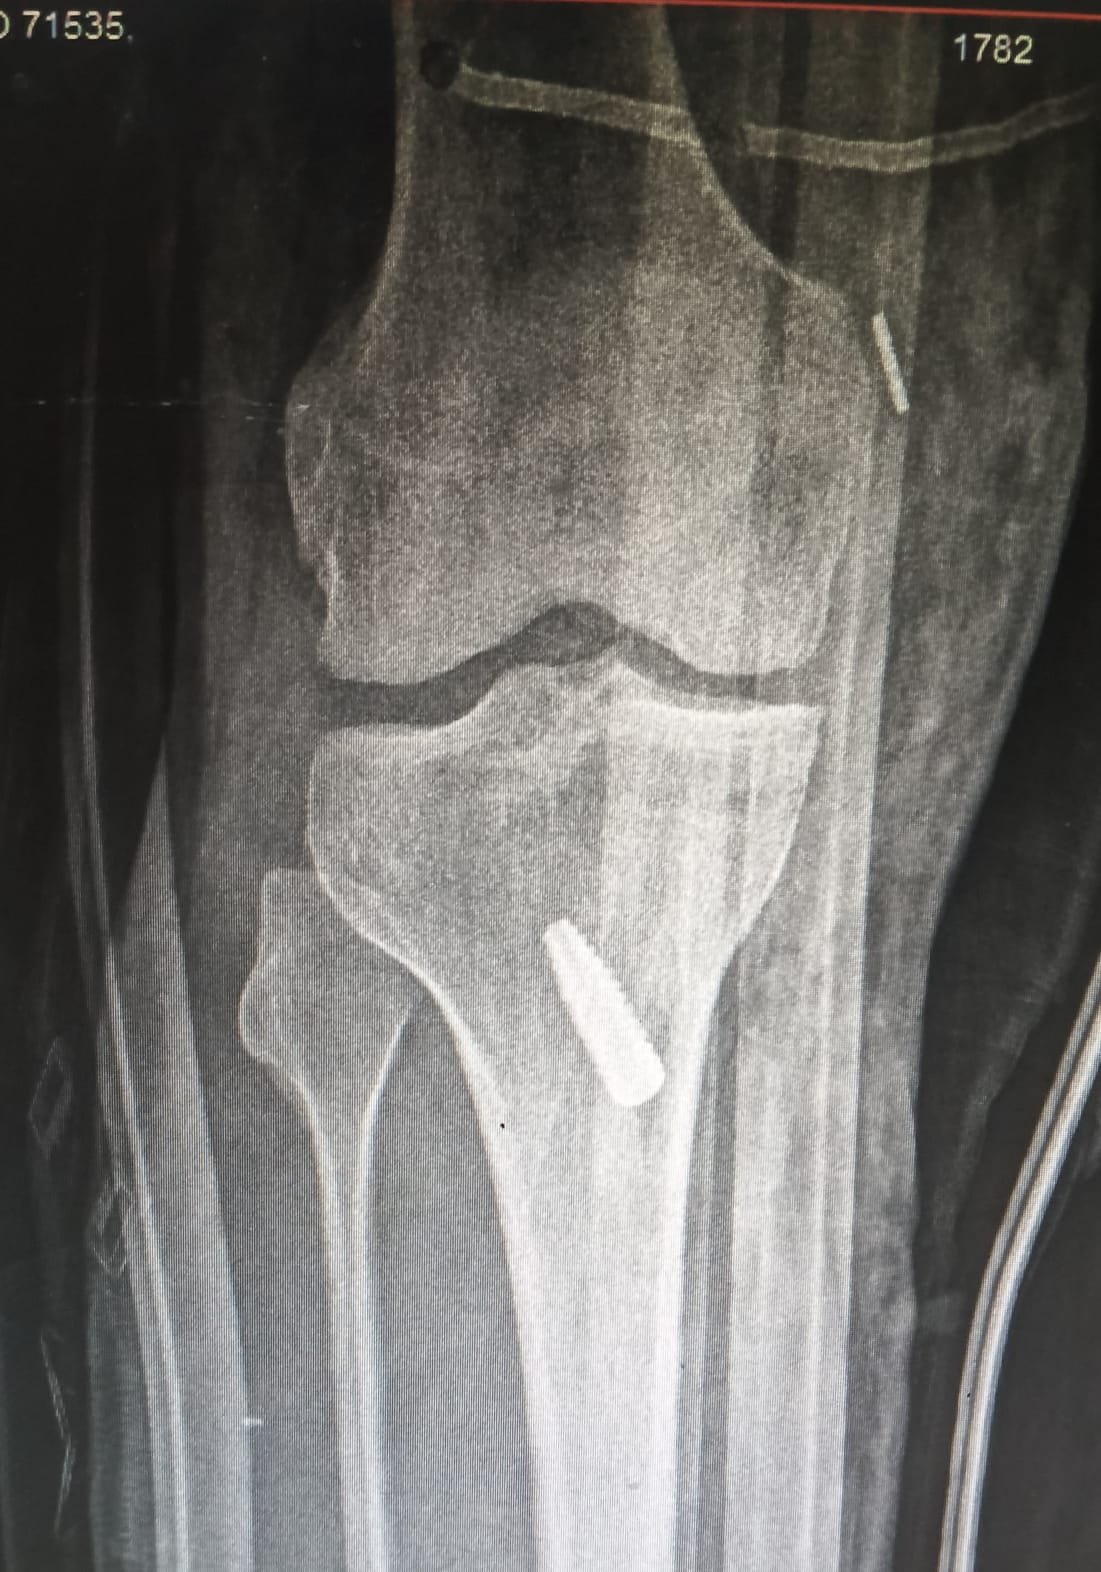

Total Knee Replacement

Gallery